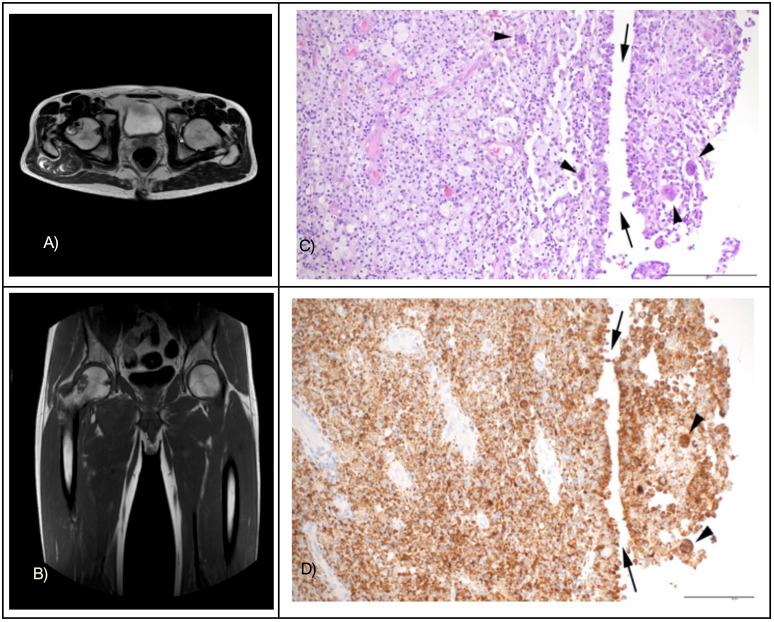

Tenosynovial giant cell tumor (TGCT) is a rare type of tumor that originates from the synovium of joints and tendon sheaths. It is characterized by recurring genetic abnormalities, often involving the CSF1 gene. Common symptoms include pain and swelling, which are not specific to TGCT, so MRI and a pathological biopsy are needed for an accurate diagnosis. We report the case of a 45-year-old man who experienced painful swelling in his right hip for six months. Initially, this was diagnosed as Erdheim-Chester disease. However, whole exome sequencing (WES) and RNA-Sequencing revealed a CSF1::GAPDHP64 fusion, leading to a revised diagnosis of TGCT. The patient was treated with pegylated interferon and imatinib, which resulted in stable disease after three months. Single-cell transcriptome analysis identified seven distinct cell clusters, revealing that neoplastic cells expressing CSF1 attract macrophages. Analysis of ligand-receptor interactions showed significant communication between neoplastic cells and macrophages mediated by CSF1 and CSF1R. Our findings emphasize the importance of comprehensive molecular analysis in diagnosing and treating rare malignancies like TGCT.

腱鞘巨细胞瘤(TGCT)是一种罕见的肿瘤类型,起源于关节和腱鞘的滑膜。其特征是反复出现基因异常,常涉及CSF1基因。常见症状包括疼痛和肿胀,但这些并非TGCT所特有,因此需要进行MRI和病理活检以准确诊断。我们报告了一例45岁男性,其右髋部疼痛肿胀6个月。最初,该病例被诊断为 Erdheim-Chester病。然而,全外显子测序(WES)和RNA测序发现了CSF1::GAPDHP64融合,从而将诊断修正为TGCT。该患者接受了聚乙二醇化干扰素和伊马替尼治疗,三个月后病情稳定。单细胞转录组分析确定了七个不同的细胞簇,表明表达CSF1的肿瘤细胞会吸引巨噬细胞。配体-受体相互作用分析显示,CSF1和CSF1R介导肿瘤细胞与巨噬细胞之间存在显著的通讯。我们的研究结果强调了全面分子分析在诊断和治疗像TGCT这样的罕见恶性肿瘤中的重要性。